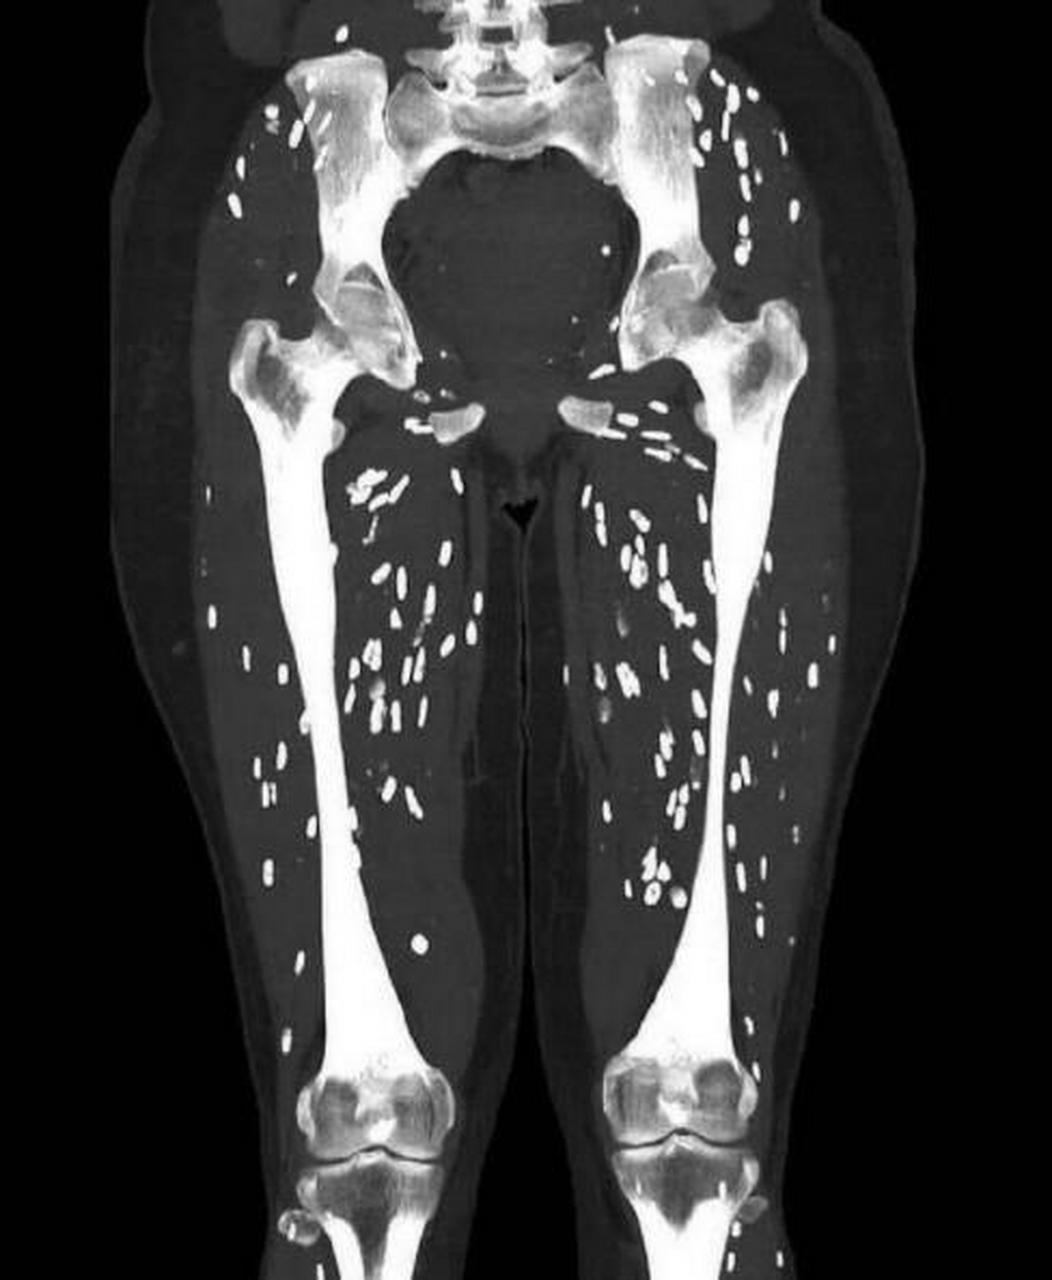

囊尾蚴病,又称囊虫病,猪囊尾蚴病,由猪带绦虫幼虫寄生于人体各组织

猪囊虫又称猪囊尾蚴虫,是猪带绦虫的幼虫,多寄生在中间宿主的横纹肌肉

不规则形囊尾蚴结构(he染色×100)诊断及鉴别因猪囊尾蚴寄生部位不同